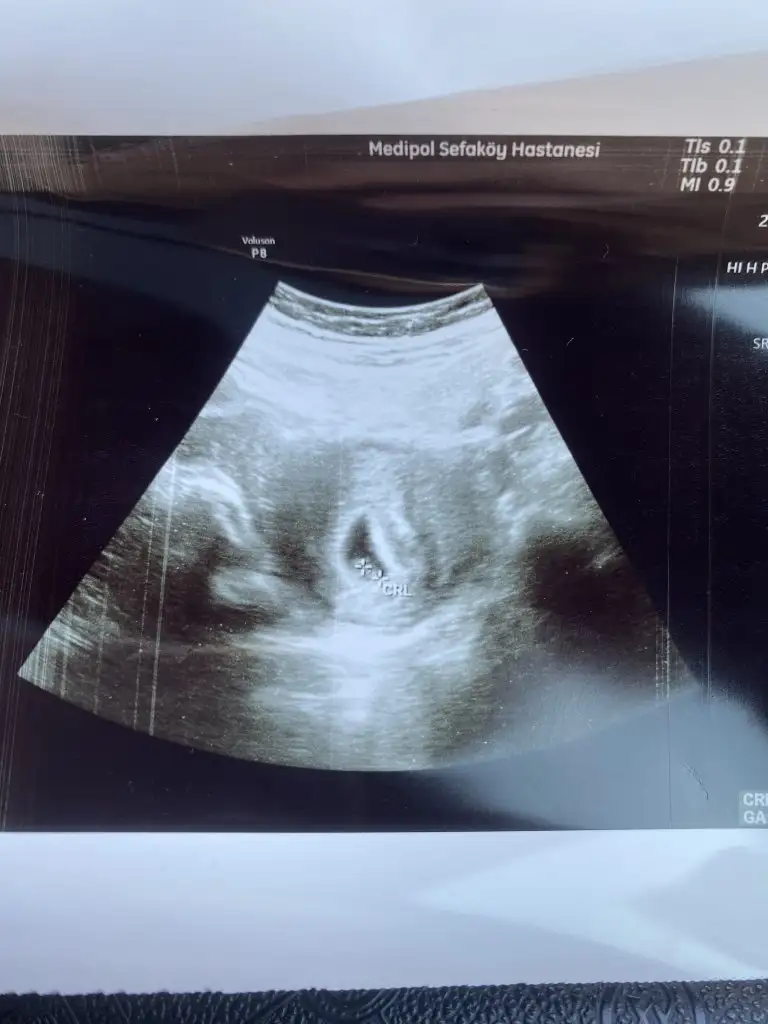

Banada bakarmısınız anlayan varsa 6+4 karından

• IMG_6407.webp